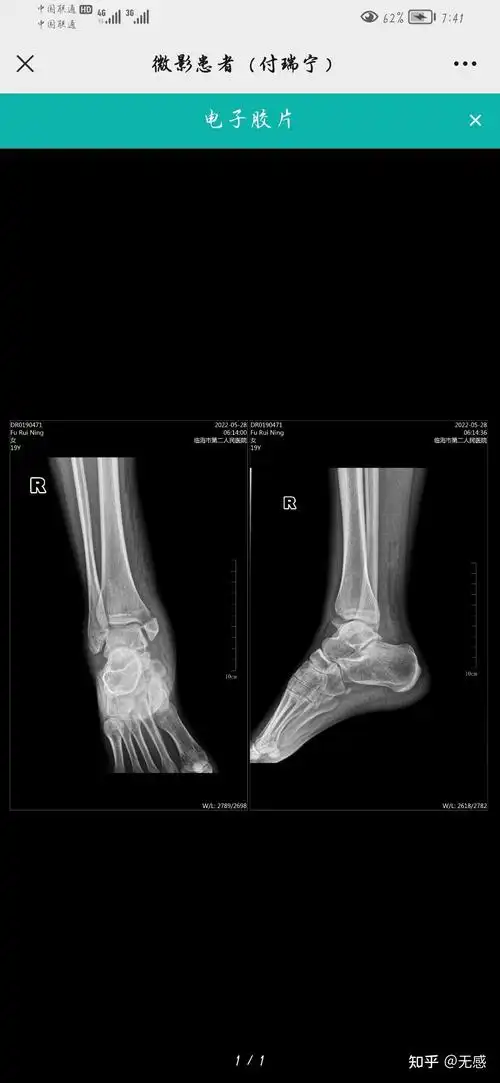

右足跟骨骨折

目前是嘛嘛的感觉,请知情者告知,谢谢!

那位好心的医生帮忙看下,这是我的ct片子,我脚是要多久可以好,现在

同仁们看看我女儿这个足x片